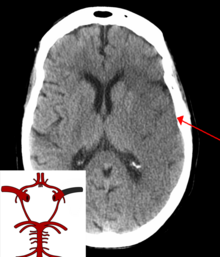

A CT showing early signs of a middle cerebral artery stroke with loss of definition of the gyri and grey white boundary

Dens media sign in a patient with middle cerebral artery infarction shown on the left. Right image after 7 hours.

Stroke is diagnosed through several techniques: a neurological examination (such as the NIHSS), CT scans (most often without contrast enhancements) or MRI scans, Doppler ultrasound, and arteriography. The diagnosis of stroke itself is clinical, with assistance from the imaging techniques. Imaging techniques also assist in determining the subtypes and cause of stroke. There is yet no commonly used blood test for the stroke diagnosis itself, though blood tests may be of help in finding out the likely cause of stroke.[63]